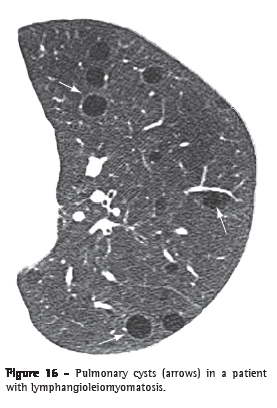

Cyst (cisto)

A cyst is any rounded, well-circumscribed space surrounded by an epithelial or fibrous wall of variable thickness.(29) On CT scans, a cyst is seen as a rounded area with low attenuation coefficient on the lung parenchyma, having a well-defined interface with the adjacent normal lung (Figure 16).(1,7) The cyst wall is usually thin (< 2 mm), but it can vary in thickness. Cysts are usually filled with air but can also contain liquid (e.g., bronchogenic cyst) or even a solid material. Diseases accompanied by multiple pulmonary cysts include lymphangioleiomyomatosis, Langerhans cell histiocytosis, lymphocytic interstitial pneumonia and Birt-Hogg-Dubé syndrome.(30,31)